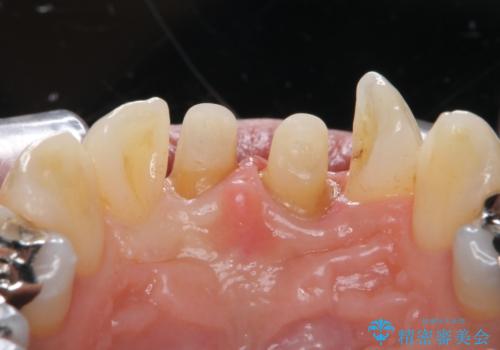

- 前歯の変色とガタつきがきになるとのことで来院されました。

矯正治療の希望はなかったため、セラミッククラウンで被せて治療していくことになりました。

元々根管治療がされていたにも関わらず被せ物が作られておらず、このままではどんどん変色が進んでいってしまう状態でした。